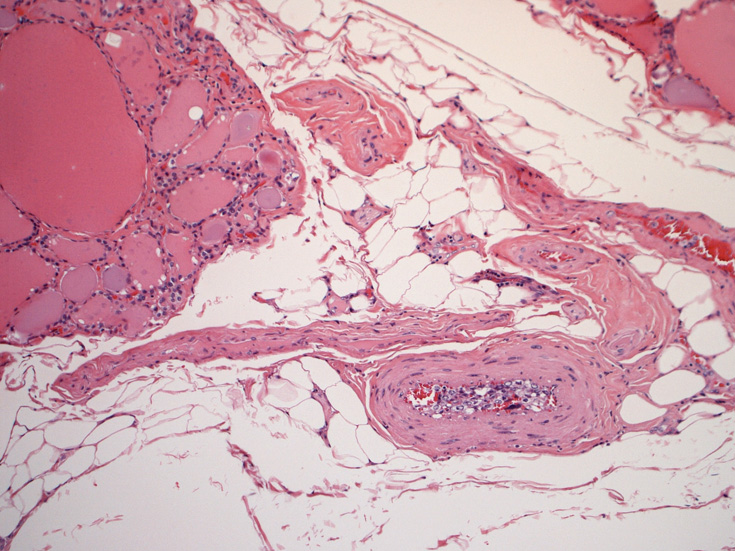

心臓;比較的大きな冠動脈内で増殖。作成した標本では心筋内細血管内には認めなかった。

肝臓;グリソン鞘内、細肝動脈に腫瘍細胞あり。肝細胞は虚血のため変性しているようです。

脾臓;白脾髄リンパ組織には腫瘍細胞は認めず、筆動脈内に増殖。

腎臓;糸球体係蹄内に腫瘍細胞が増殖するほか細腎動脈にもみとめられる。

膵, 甲状腺;細動脈内の腫瘍細胞. 大腸;粘膜下細動脈内に腫瘍細胞を見る。

副腎;類洞内に腫瘍細胞がびまん性増殖し, 副腎が腫大している。